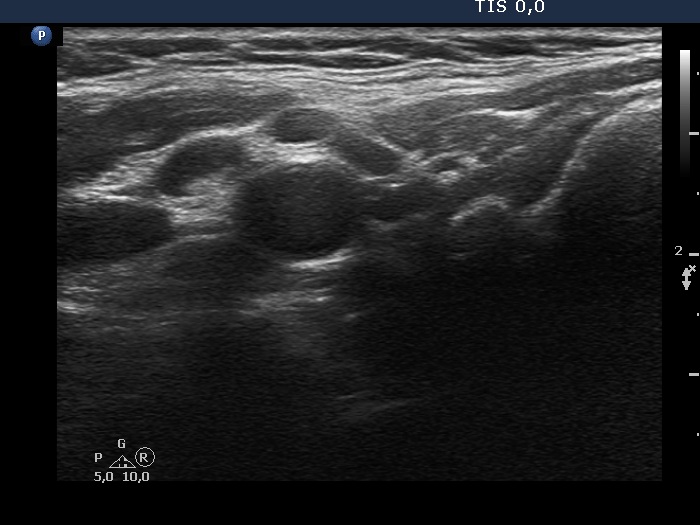

Ultrasonography. The thyroid was echonormal. There was a hypoechogenic nodule in the right lobe. The nodule had numerous punctate echogenic granules.

The echogenic figures are very difficult not to interpret as microcalcifications. Nevertheless, thorough analysis reveals that some of the bright granules has a short tale, and great proportion of these figures are related to ventral tiny hypoechoic areas, probably cysts. Moreover, there are not only echogenic granules but also short echogenic lines within the nodule. Taking all in all, these echogenic figures are very suspicious being microcalcifications.

- The ACR TIRADS is the only one which does not use the term 'microcalcification', instead they use the term 'punctate echogenic foci', which includes microcalcifications and short-tail comet-tail artifact. This example stands for the advantage of the ACR terminology.

- In such nodules it is to be considered to delay the ultrasound report till the result of FNA. In this patient FNA disclosed benign colloid goiter and there were macrophages on the smear. The latter proved that the nodule had cystic areas. If we take this fact into account, than it can solve our concern about the interpretation of echogenic granules.